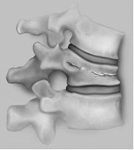

Die weitaus meisten Rückenprobleme sind duch einen relativ früh beginnenden Verschleissprozess der Wirbelsäule bedingt.